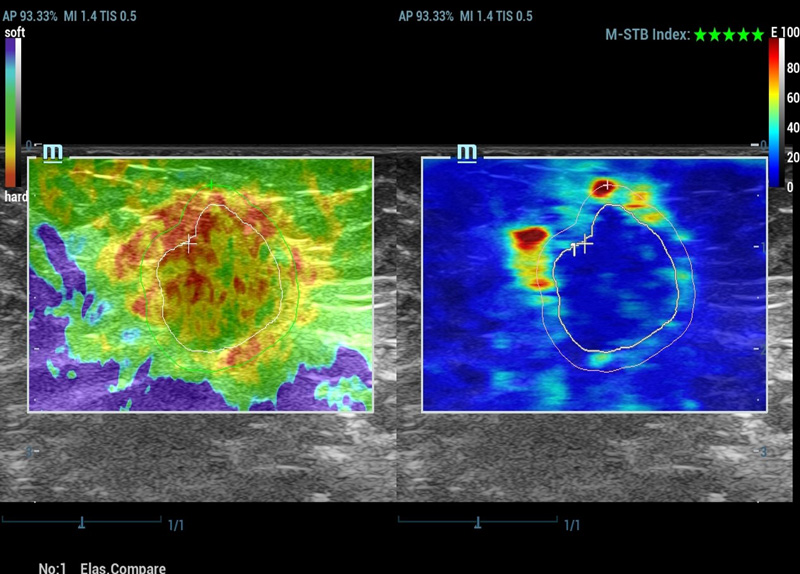

M-Reference E Compare

Strain en shear-wave inspireren samen de toekomst

M-Reference Multi-parametrische analysetools

M-Ref. C&E ondersteunt het weergeven van het contrast en de STE in ├®├®n vlak voor vergelijkende beoordeling van perfusie en elasticiteit.

M-Ref. E Compare

M-Ref. E Compare ondersteunt het weergeven van zowel de realtime strain-elastografie als STE in ├®├®n vlak voor de evaluatie van weefselstijfheid.

Strain-elastografie

- Hoge gevoeligheid, productiviteit, penetratie en nauwkeurigheid

- Unieke 'schil' voor de analyse van het infiltratiegebied van de tumor

Strain-elastografie